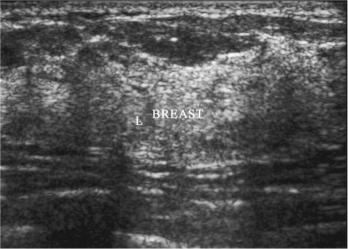

图8-3 乳腺增生声像图

乳腺腺体局限性增厚,边界光滑,内部未见占位